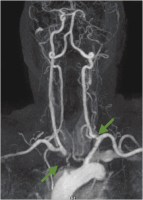

Subtraktionsangiographie

Abbildung 10: Subtraktionsangiographie. Hochgradige Abgangsstenose der rechten Art. vertebralis.

Abbildung 11: Subtraktionsangiographie. Hochgradige, exzentrische Abgangsstenose der rechten Art. carotis interna (grüner Pfeil).

Kontrollangiographie

Abbildung 12: Intraoperative Kontrollangiographie nach simultaner Eversionsendarterektomie der rechten Art. carotis interna und Transposition der rechten Art. vertebralis in die rechte Art. carotis communis (roter Pfeil).

Abbildung 13: Intraoperative Kontrollangiographie in einer 2. Ebene nach simultaner Eversionsendarterektomie der rechten Art. carotis interna (roter Pfeil) und Transposition der rechten Art. vertebralis in die rechte Art. carotis communis (roter Pfeil).